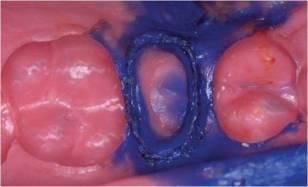

- Allungamento di corona

Applicazioni Cliniche